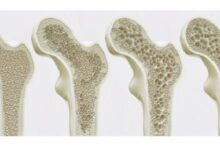

هشاشة العظام، أو الهشاشة، أو تخلل العظام، أو تنخر العظم (بالإنجليزية: Osteoporosis) هي حالة صحية تصبح فيها العظام تدريجياً أكثر ضعفًا وهشاشة، ممّا يعني أنّ هذه العظام تكون أكثر عرضة للإصابة بالكسور (بالإنجليزية: Fractures)، وإنّ الإصابة بهشاشة العظام لا تعني وجود كسور في عظام الجسم بصورة قطعية، لكنّها تعني أنّ المصاب معرّض للإصابة بكسور العظام بصورة أكبر، وفي الحقيقة يُعدّ مرض هشاشة العظام من الأمراض الشائعة لدى النساء أكثر من الرجال.[١٨]